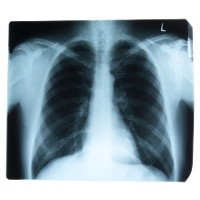

Para peneliti dari Norwegian University of Science and Technology and Trondheim University menulis bahwa pasien kanker paru-paru seringkali memiliki penyakit lain, salah satunya adalah diabetes.

Namun bukti tentang dampak diabetes pada kelangsungan hidup kanker paru-paru ternyata cukup bertentangan, sehingga megusik rasa ingin tahu peneliti untuk melakukan kajian ini.

1. Tingkat kelangsungan hidup 1 tahun pada pasien kanker paru-paru yang juga menderita diabetes adalah sebesar 43%, dibandingkan dengan 28% pada mereka yang tidak mengidap diabetes.

2. Tingkat kelangsungan hidup 2 tahun pada pasien kanker paru-paru yang menderita diabetes 19% dan 11% pada yang tanpa diabetes.

3. Tingkat kelangsungan hidup 3 tahun pada pasien kanker paru-paru dengan diabetes 3% dan tanpa diabetes 1%.

4. Ketika variabel-variabel lainnya seperti jenis kelamin, usia, stadium penyakit, dan rasio bahaya disesuaikan, kelangsungan hidup pasien kanker paru-paru dan diabetes melitus adalah 0,55 dan menunjukkan bahwa pasien kanker paru-paru tanpa diabetes hampir dua kali lebih banyak yang meninggal dibandingkan dengan pasien kanker paru-paru dengan diabetes.

Seperti dilansir Medical News Today, Selasa (18/10/2011), para peneliti kemudian menyimpulkan bahwa pasien kanker paru-paru dengan diabetes mellitus memiliki kelangsungan hidup yang lebih tinggi dibandingkan dengan yang tidak mengidap diabetes mellitus. Tak hanya itu, peneliti juga menemukan bahwa pasien dengan diabetes memiliki tingkat kanker metastatik atau penyebaran tumor yang lebih rendah.

Awalnya mereka berpikir mungkin inilah yang dapat menjelaskan mengapa pasien dengan diabetes dapat bertahan hidup lebih lama, karena kebanyakan pasien kanker paru-paru tidak mati akibat tumor primer tetapi tumor sekunder.

Tetapi ketika diselidiki lebih lanjut, ternyata tidak sesederhana itu, sebab kesemua pasien kanker paru-paru dengan diabetes melitus juga menderita kanker paru-paru stadium lanjut. Inilah sebabnya peneliti menyarankan perlunya lebih banyak penelitian yang harus dilakukan.